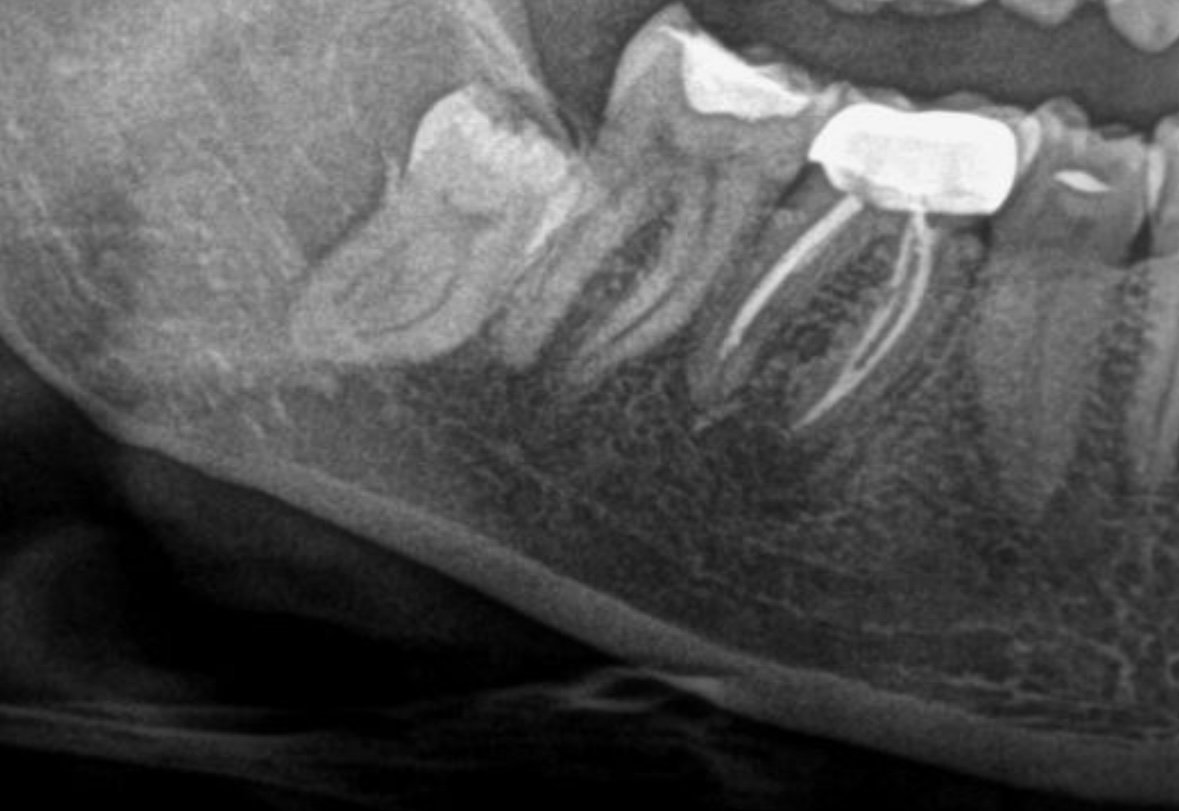

Вчера ме приеха с болницата и снощи беше операцията за премахване на долен мъдрец . Днес не си усещам зъбите ,половината устна и брадичката . Доктора каза ,че мъдреца е бил оплетен в нерв ,нерва не е скъсан ,но няколко дни щяло да бъде така . Това нормално ли е ? Дали въобще ще се оправи ? Също така имам болка към гърлото . Доктора каза че е била трудна операция . Доста ме шиха .не знам какво да очаквам

На мен при допир с нерва ми изписаха Милгама

При ваденете на първият ми мъдрец около седмица не си чувствах дясната долна половина. След това постепенно започна да ми се връща чувствителността, но до пълно възстановяване минаха около 4 месеца.

След ваденето на вторият се възстанових за 2 дни.